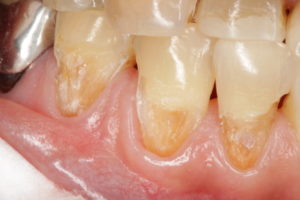

今日は、よくある症例をお見せします。歯の根元が、茶色くなってしまっている方いらっしゃいませんか?これは、歯肉がやせて歯の根が露出した後に起こる症状です。歯の根の虫歯ですね。

しかし、これをきれいに治すのが意外と難しいんです。特に、歯肉との境目をきれいに仕上げるのは至難の業です。この症例は、治したところの色と形態がマッチしていなかったためやり直しをしたものです。